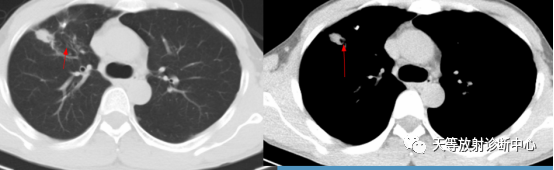

▲结核球型:具有尖角及刀切改变。

▲结核结节的近端空洞及支气管引流方向。

▲结核结节钙化灶。

▲结核结节无强化型,偏心侧空洞。

▲结核结节无强化型。